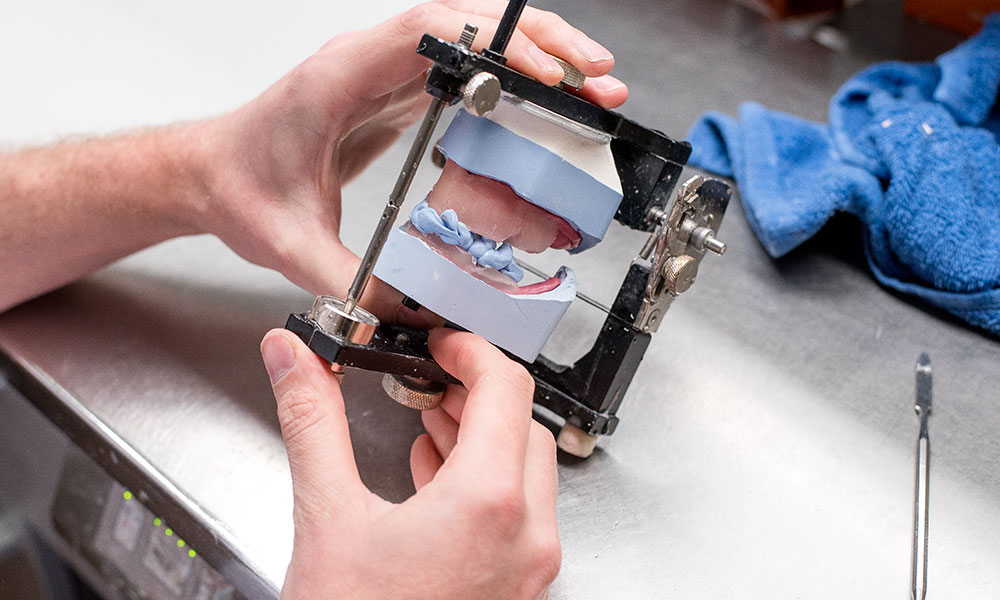

Een klikgebit is een kunstgebit dat vast zit op implantaten. Implantaten zijn kunstwortels die in de kaak geplaatst worden als een schroef. Er zijn verschillende systemen waarop het kunstgebit op de implantaten vast gezet kunnen worden, hieronder ziet u de twee meest voorkomende systemen.

Drukknoppen

Steg

De implantaten zullen dan eerst geplaatst worden en daarna maken wij voor u het klikgebit op de implantaten.